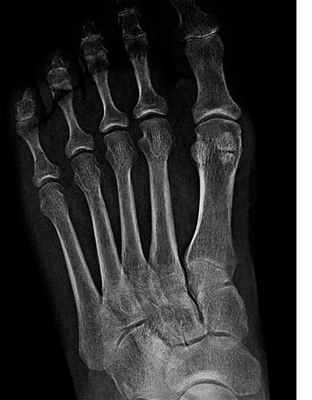

Рис. 2. Рентгенограмма правой стопы. По внутреннему краю расположена большеберцовая или медиальная сесамовидная кость, по наружному краю – малоберцовая или латеральная сесамовидная кость

— Os hallux — две постоянные сесамовидные кости в области соединения первой плюсневой кости с первым пальцем (внутри сухожилия короткого сгибателя большого пальца стопы). Они увеличивают рычаги воздействия сухожилий сгибателей на фаланги первого пальца, а также снижают силу трения сухожилий о мягкие ткани в положении разгибания первого пальца.

— Сесамовидные кости также иногда обнаруживаются в плюсне-фаланговых суставах второго и пятого пальцев, иногда в суставах третьего и четвертого пальцев и в межфаланговом суставе большого пальца.

На стопе под 1 плюснефаланговым суставом имеются две сеcамовидные кости. Каждая кость может состоять из двух долей, которые отделены друг от друга, что считается вариантом нормы. Сесамовидные кости представляют собой опору для сухожилий сгибателей большого пальца. Сесамовидные кости своей массой увеличивают расстояние от сухожилия до центра вращения 1 плюсне-фалангового сустава. Происходит увеличение рычага силы сгибания пальца и увеличение момента мышц, которые сгибают большой палец, что необходимо для отталкивания от опоры.